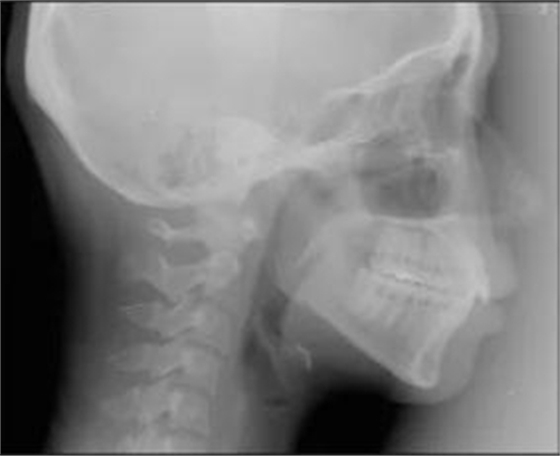

五、治療結(jié)果

治療后數(shù)據(jù)提示治療目標(biāo)達(dá)成。面相結(jié)果提示微笑及側(cè)貌得到改善(圖6)。達(dá)到了安氏I類尖牙關(guān)系和安氏II類磨牙關(guān)系,形成尖牙保護(hù)合。牙齒中線無偏斜,達(dá)到理想的覆合覆蓋,Spee曲線得到整平。

治療后全景片提示間隙得到關(guān)閉,除了左下頜第一前磨牙外牙根平行度可,無明顯骨及牙根吸收。(圖7)